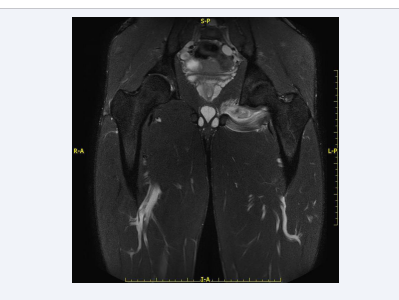

The exam highlighted extensive signal alteration of the left obturator externus muscle that almost completely affects the entire muscular element. This signal hyperintensity was expression of interstitial hemorrhage between tertiary fibers, associated with edema. In central area the hyperintensity had an inhomogeneous appearance and the signal had a slightly reduced intensity for an extension of about 24 mm, expression of real muscle damage. Signal alteration also affected the adjacent margin of obturator internus muscle, by contiguity. In DWI acquisitions, a reduction of diffusivity involving the muscle was observed (Figure 1).

MRI coronal STIR TSE weighted image shows signal  alteration of the entire obturator externus muscle, (type 3 lesion).

Figure 1: MRI coronal STIR TSE weighted image shows signal alteration of the entire obturator externus muscle, (type 3 lesion).

These findings were expression of a type 3 lesion of the obturator externus, without serum-blood collection, with marginal peripheral involvement of the obturator internus.